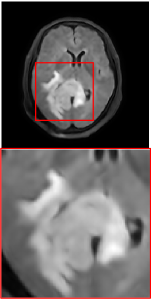

Figure 5 provides the qualitative comparison of the various methods on the four datasets at a scale of 4. The top, second, third, and bottom rows are the SR results under the FastMRI, clinical brain, clinical tumor and clinical pelvic datasets, respectively. The red boxes indicate the zoom-in region of complicated anatomical structures along with their corresponding error maps. Note that the brighter textures in the error maps, the lower the quality of the reconstructed images. As can be seen, compared to methods based on Transformers and CNNs, diffusion-based methods like DisC-Diff and DiffMSR (Ours) are capable of reconstructing high-realistic images with promising reconstruction metric scores (PSNR and SSIM). Nevertheless, while DisC-Diff can reconstruct high-precision MR images, it does not preserve the structure present in the original HR images, introducing some additional information that can affect medical diagnosis. In contrast, our method combines DM and PLWformer, which can preserve the original image’s structure while restoring high-frequency information.

In this section, we present more visual qualitative comparisons. Figures 8, 9, 10, and 11 show the reconstruction results of each method in FastMRI, clinical brain, clinical tumor, and clinical pelvic, respectively. As can be seen, although DisC-Diff can reconstruct MR images with high-frequency information, it fails to preserve the structure and content of the original Target HR image effectively, resulting in image distortion. In contrast, our proposed DiffMSR can restore high-frequency information while preserving the structure of the original HR image, indicating the effectiveness of the joint use of DM and PLWformer.